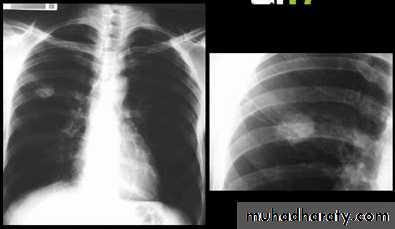

Nodular (coin) lesion in the left upper lung with irregular edge (most probably cancinoma